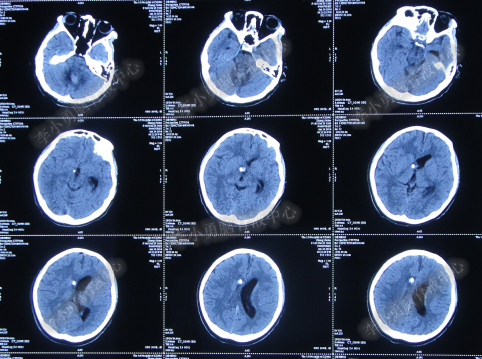

第3次手术右侧脑室外引流术后1个月时间内,脑积水仍没有得到控制,再给予腰大池引流,期间多次试图拔除右侧脑室外引流管(多次调高脑室外引流管的高度),但因患者意识变差,而无法拔除引流管,给予拔除腰大池引流,治疗期间曾多次查头部CT均示脑积水仍无改善(图-20、图-21、图-22、图-23)。

图-20:2014年7月24日头部CT

图-21:2014年7月29日头部CT

图-22:2014年8月4日头部CT

图-23:2014年8月15日头部CT